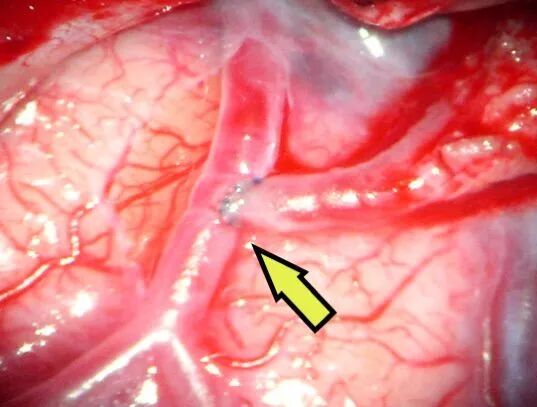

箭头所示为颞浅动脉额支(供血动脉)与右侧大脑中动脉M4段(受体)经精密的缝合吻合到一起(血管直径只有0.8mm)。